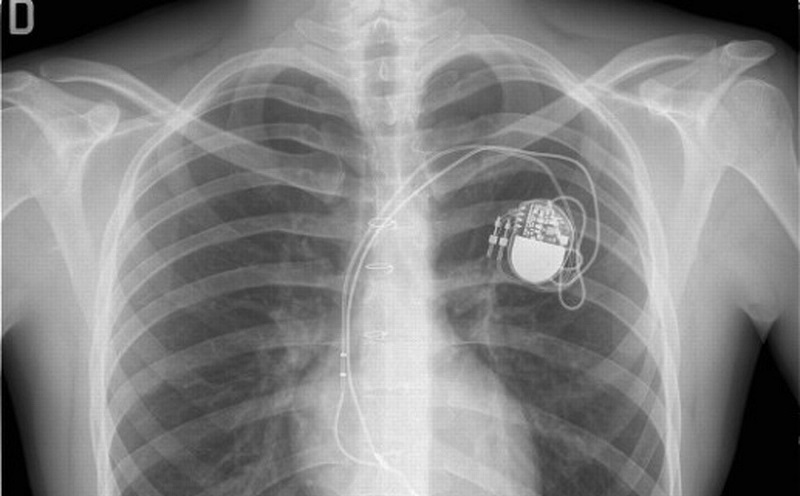

Το ζήτημα που προκάλεσε το ενδιαφέρον των ερευνητών ήταν ότι ο κατηγορούμενος είχε μια σοβαρή καρδιακή πάθηση και άλλα ιατρικά θέματα που θα καθιστούσαν εξαιρετικά δύσκολο για αυτόν να προβεί σε όλα αυτά που είχε δηλώσει και έτσι η αστυνομία κατάφερε να εξασφαλίσει ένταλμα έρευνας για τα δεδομένα του βηματοδότη του.

Σύμφωνα με έγγραφα του δικαστηρίου, ο καρδιολόγος που τον παρακολουθούσε και εξέτασε τα στοιχεία από τον βηματοδότη πριν και κατά τη διάρκεια της πυρκαγιάς, δήλωσε πως: “… Είναι εξαιρετικά απίθανο ο κ. Compton να ήταν σε θέση να συσκευάσει και να μεταφέρει τον αριθμό των πραγμάτων που ισχυρίζεται από το σπίτι του, να βγει από το παράθυρο του υπνοδωματίου του και να κουβαλήσει πολλά μεγάλα και βαριά αντικείμενα στο μπροστινό μέρος της κατοικίας του λόγω της κατάστασης της υγείας του.

” Στη συγκεκριμένη περίπτωση τα ιατρικά δεδομένα αποτέλεσαν καθοριστικό παράγοντα των στοιχείωνγια τον κατηγορούμενο, παρόλο που ανιχνεύτηκαν και ίχνη βενζίνης στα ρούχα και τα παπούτσια του. Η φωτιά προκάλεσε ζημιές $ 400.000. Η δικηγόρος του Compton αναφέρει είτε ένοχος είτε όχι περιπτώσεις όπως αυτή “θα μπορούσε να είναι η αρχή για μεγαλύτερες επιπτώσεις στην ιδιωτική ζωή από τη χρήση ιατρικών δεδομένων ενός ατόμου.” Εξήγησε: «Οι Αμερικανοί δεν θα πρέπει να έρθουν στη θέση να επιλέξουν με μεταξύ υγείας και ιδιωτικότητας. Σαν κοινωνία πρέπει να διατηρούμε το διαίωμα του απορρήτου των προσωπικών και ιατρικών πληροφοριών. Όταν αναγκάζουμε τους πολίτες να παραδώσουν προστατευμένα δεδομένα υγείας για την επιβολή του νόμου καταργούμε το δικαίωμα αυτό των πολιτών.”